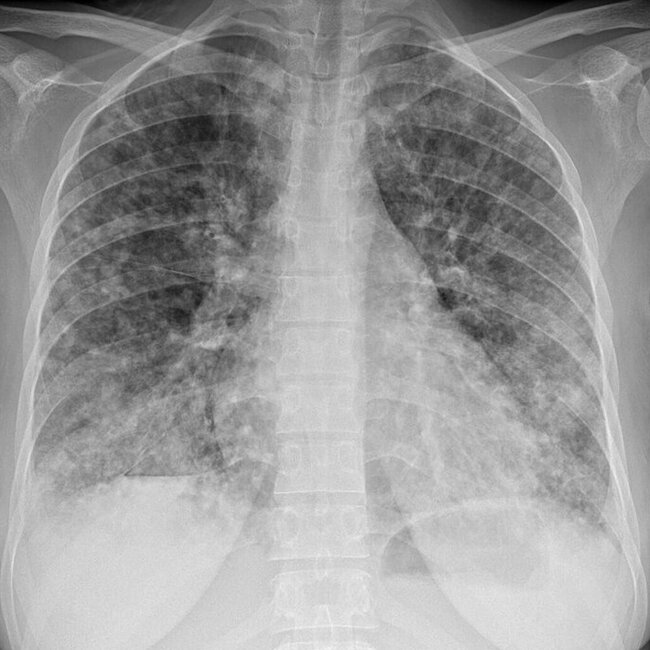

Пациент быстро направлен на МСКТ органов грудной клетки - картина бластоматозного образования с деструкцией лопатки, метастатического поражения легких.

Всем курильщикам со стажем, делайте МСКТ органов грудной клетки, хотя бы 1 раз в год, на флюорографии ничего не видно, а когда появляются симптомы уже поздно.